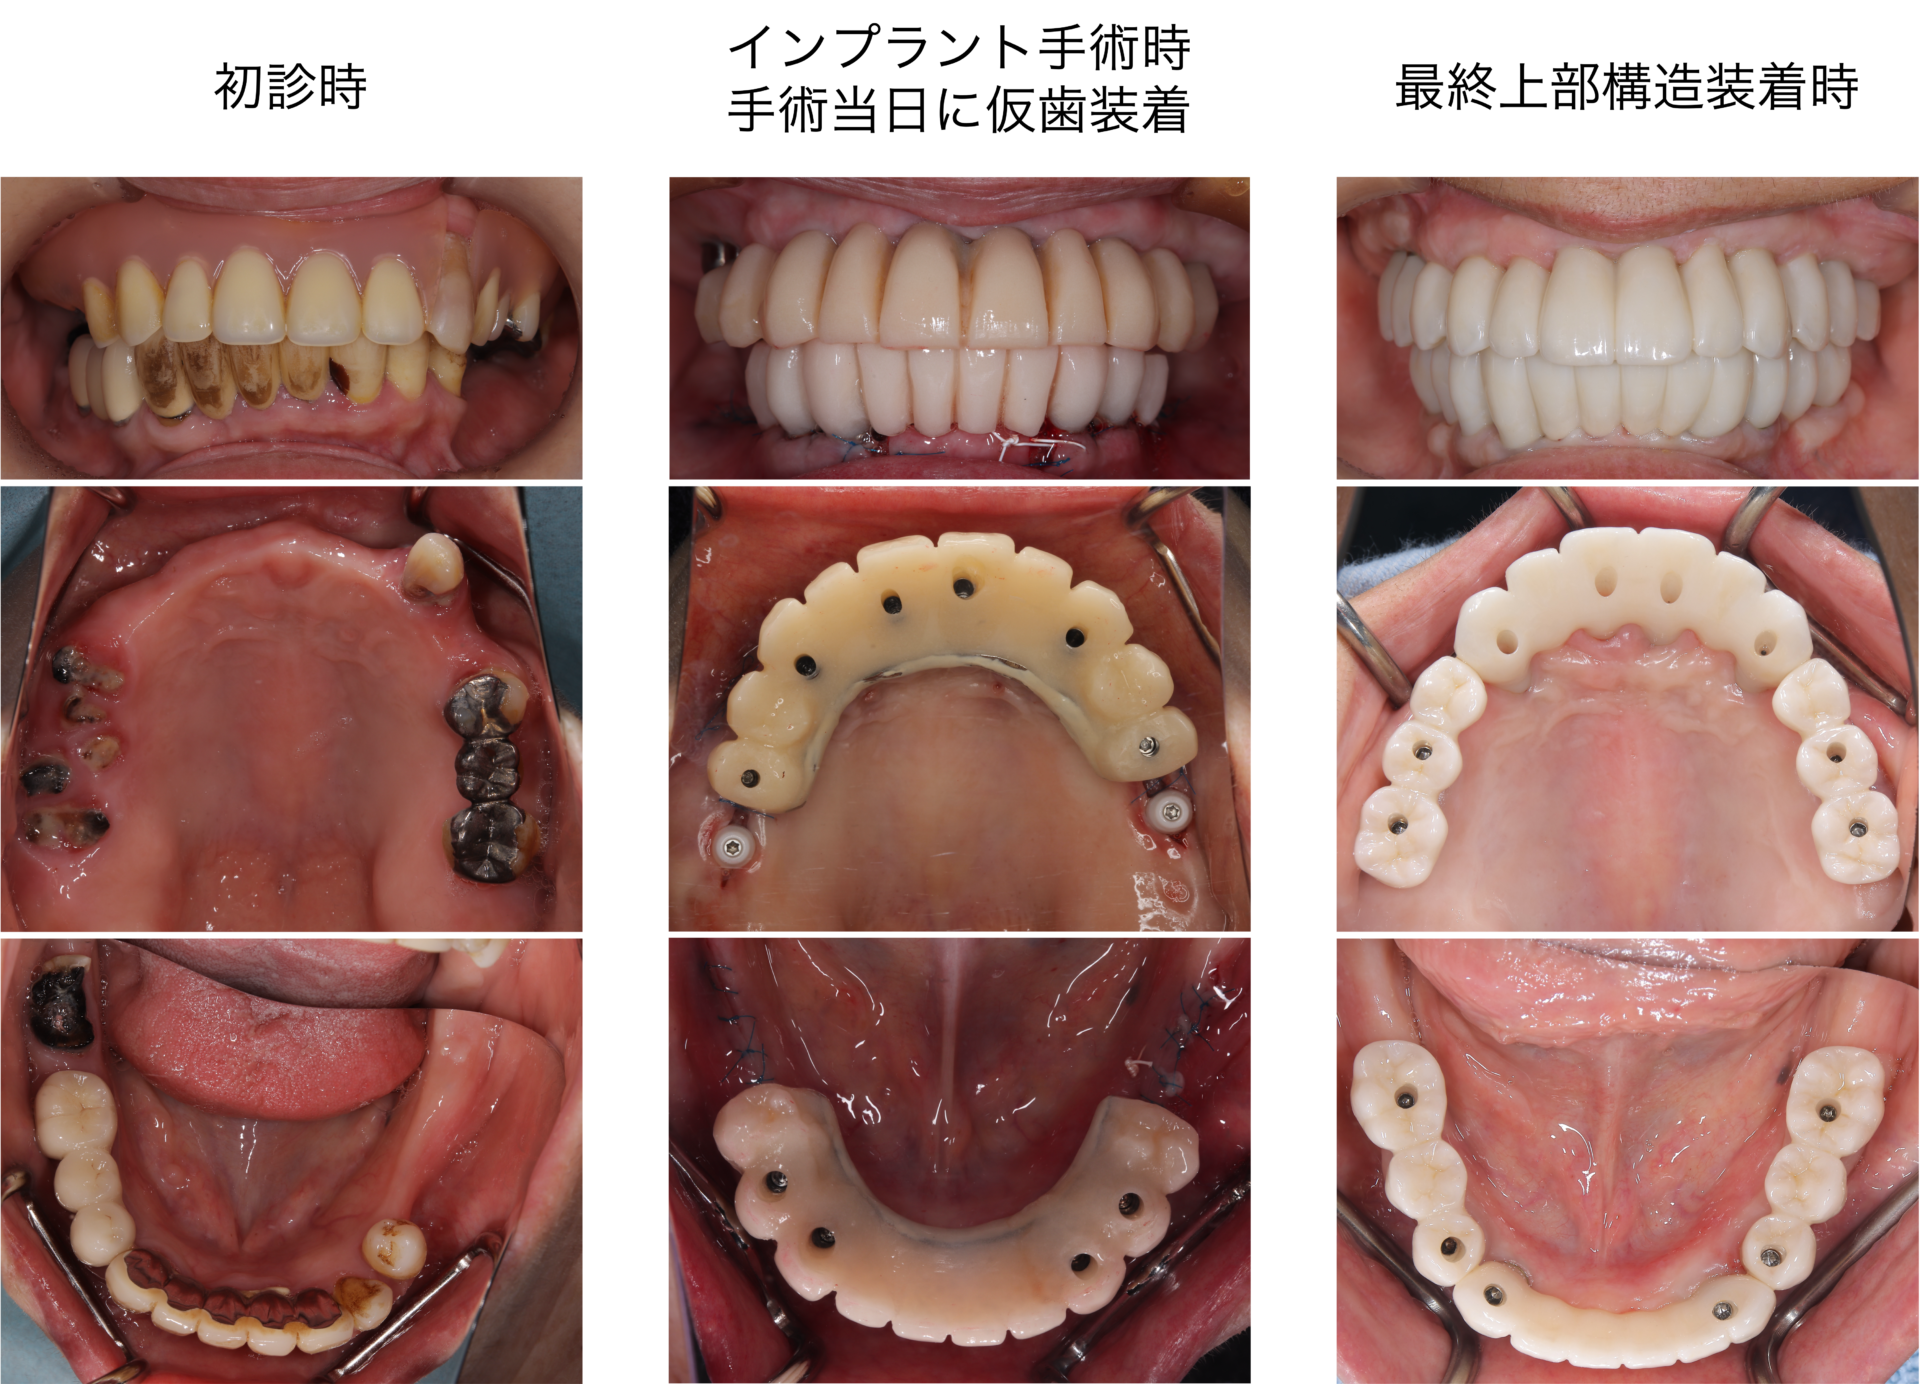

本日は、上顎の骨が少ない方にインプラント治療を行った治療を紹介させていただきます こちらの患者様は、上顎の大臼歯に欠損がありインプラント治療を希望されていらっしゃいましたしかしながら一般的な長さのインプラントを埋め込むには上顎の骨の高さが不足しており、インプラントの先端1/3が上顎洞(鼻の横の空洞)に突き出してしまうという診断となりました このような現存する …